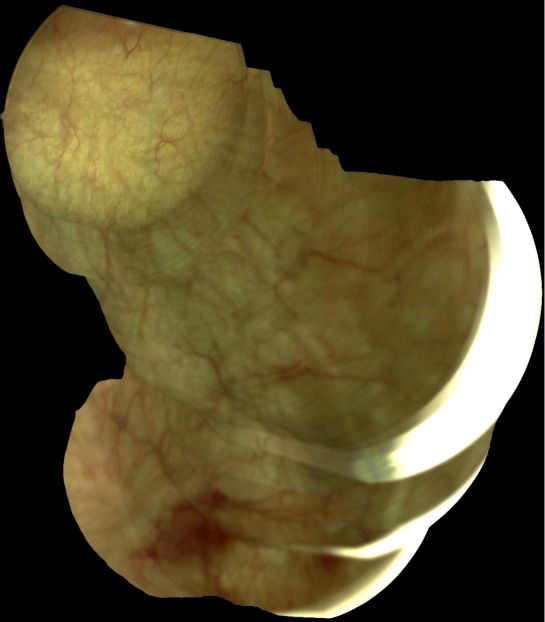

To validate the effectiveness of the proposed descriptor in generating panoramic images, we feed the obtained matching results to a mosaicing system based on RANSAC algorithm [Fischler & Bolles, 1981]. We construct a panoramic image with a set of 400 consecutive frames from bladder endoscopic video, as shown in Figure 10.

Refer to caption

Figure 10: A 1258×1436125814361258\times 1436 panoramic image constructed from a 400 consecutive frames from human bladder endoscopic video. The obtained mosaic image is coherent and we can observe clearly the texture continuity which is a good indicator proving the precision of the images alignment.

The obtained mosaic image is coherent and we can observe clearly the texture continuity which is a good indicator proving the precision of the images alignment. This experiment illustrates that the proposed descriptor provide reliable and robust matching features that can be utilized to construct panoramic images for endoscopic videos. However, a strong blur effect or large scale change can perturb the registration process and cause discontinuities in the resulting mosaic image. To overcome this problem, we can extend the mosaic image system with an artifact detection algorithm.